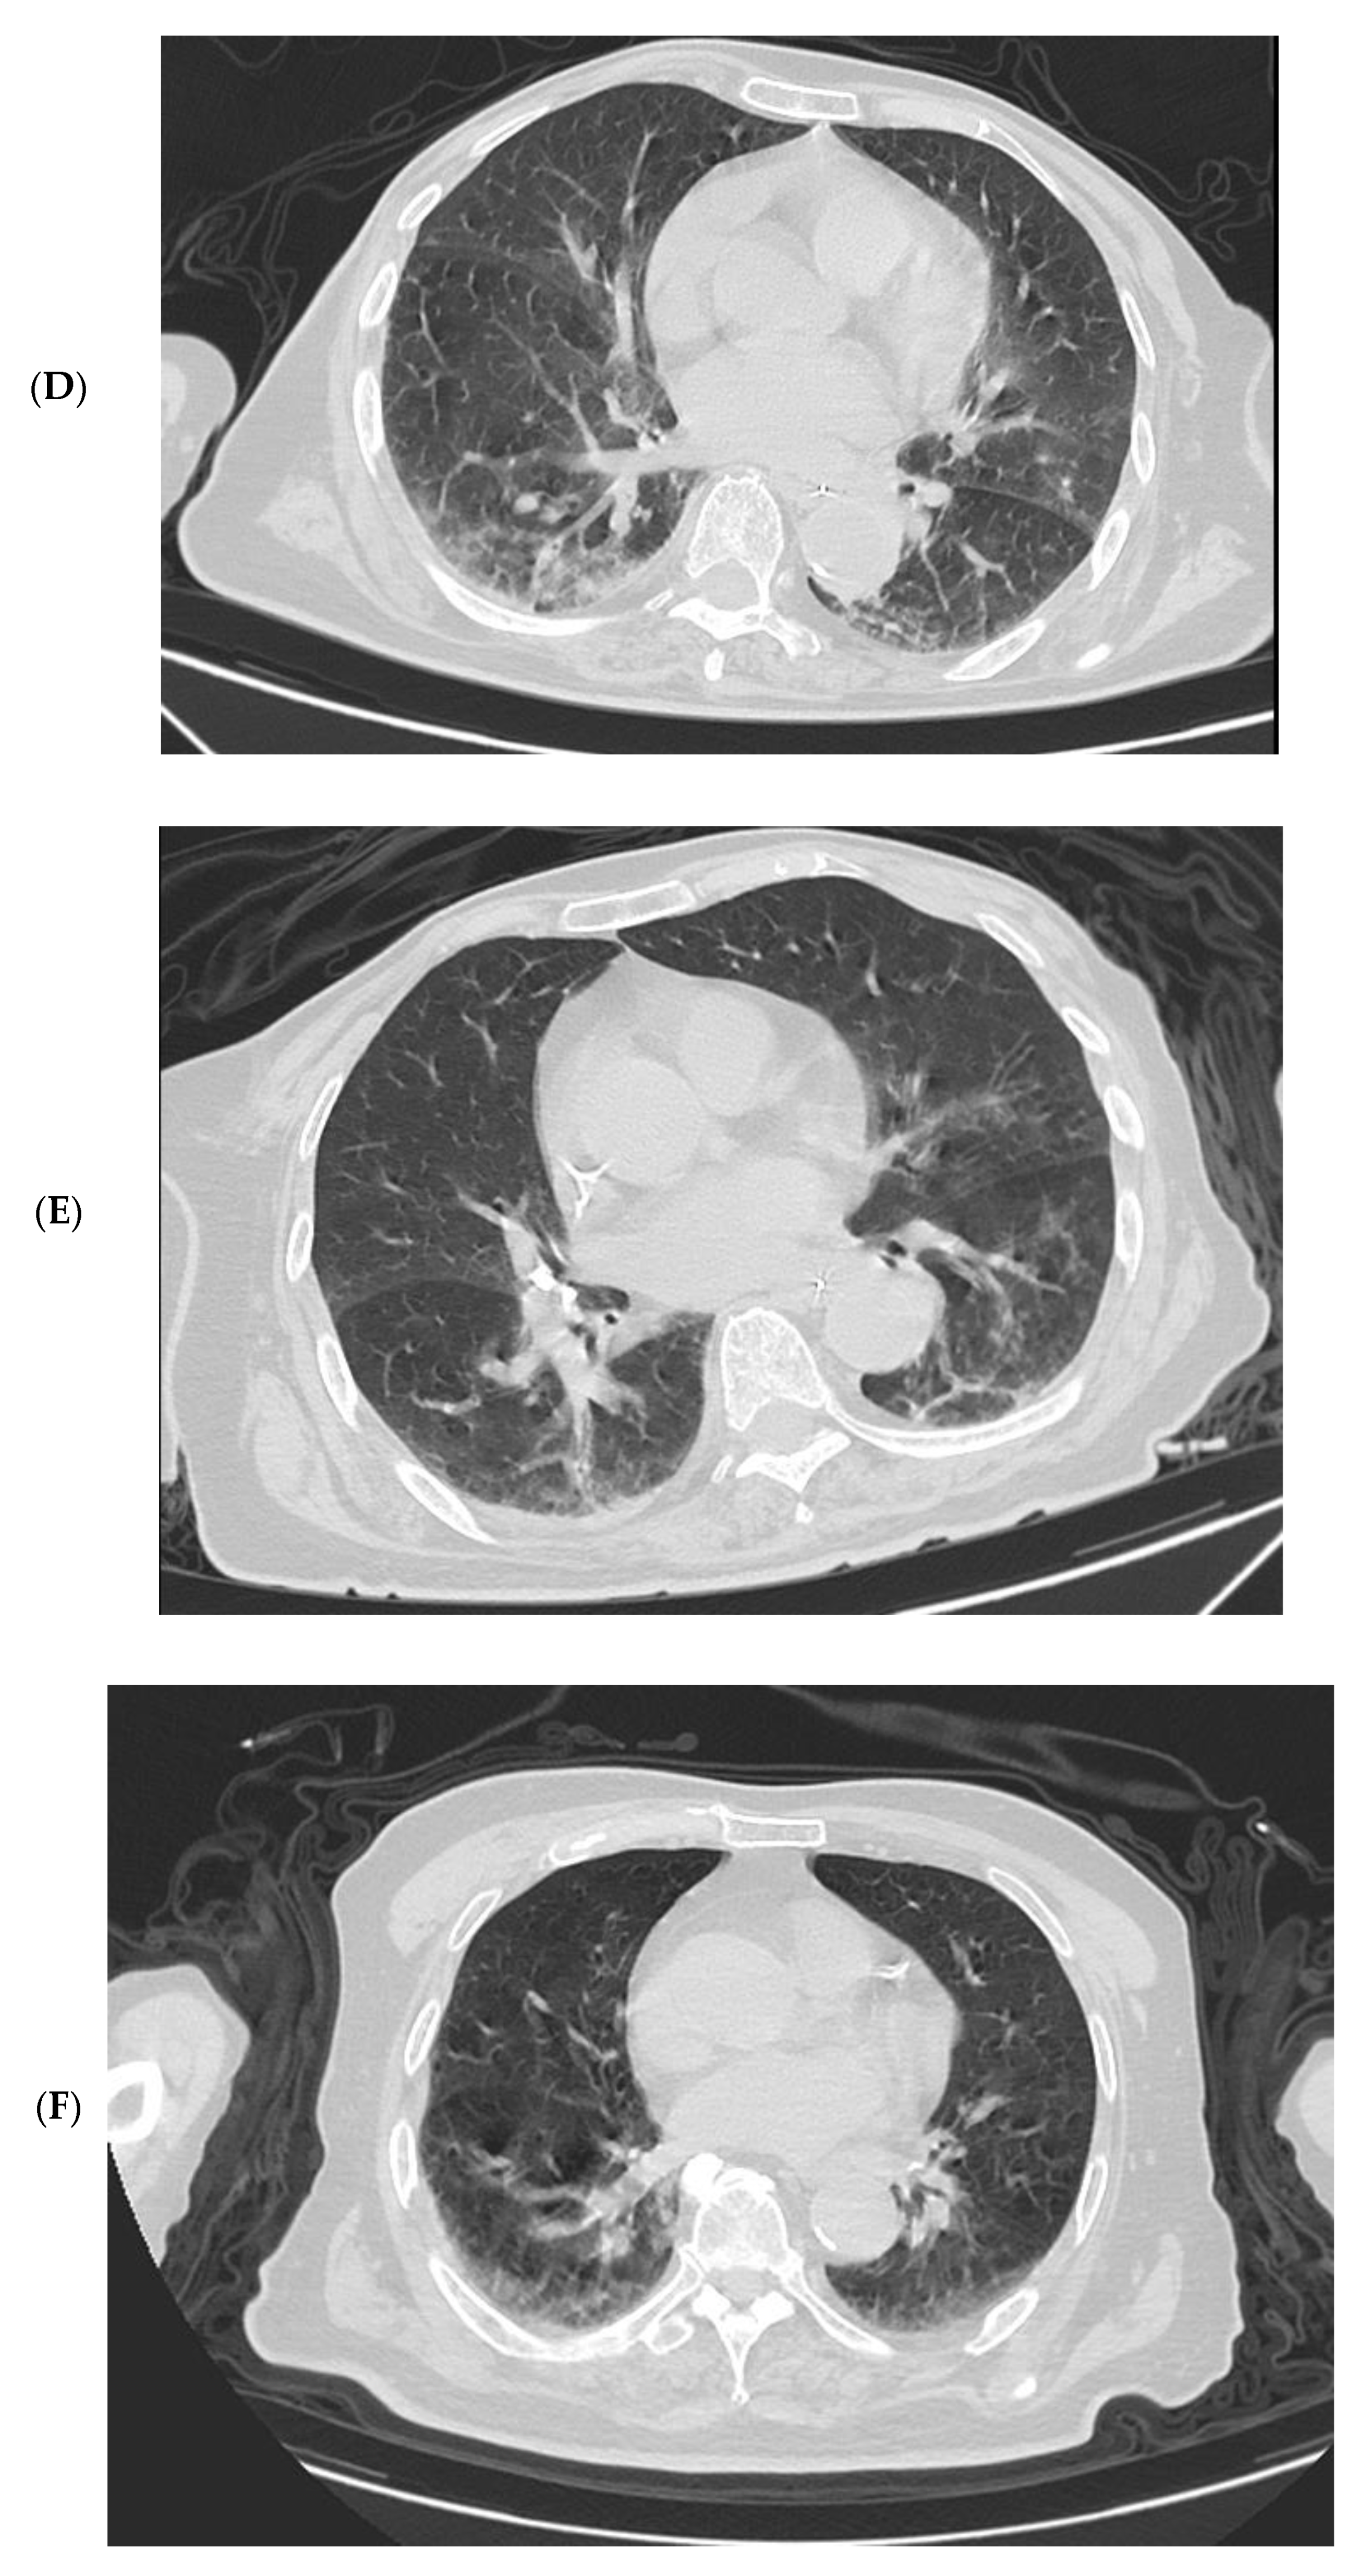

3.4. Imaging Changes in Disease Progression